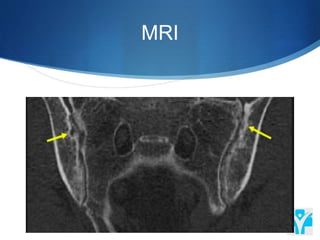

MRI

When to orderMRI? To diagnose inflammatory arthritis Patients with previous history of lumbar spine surgery (to exclude infection or nerve root compression resulting from scar tissue) Vertebral fracture

• #16 MRI studies -25% to 50% of individuals without low back pain will have a disk bulge or protrusion at one or more lumbar disk levels. Consequently, disk bulges/protrusions on MRI in patients with low back pain are usually coincidental, whereas disk extrusion, especially with compression of the lumbar nerve, is usually a significant cause of